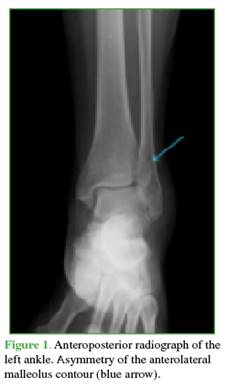

A 62-year-old housewife, previously independent in her self-care and household activities, with non-insulin-dependent type 2 diabetes mellitus, controlled arterial hypertension, and asymptomatic bilateral hallux valgus, presented to the Emergency Department of our institution after suffering an inversion trauma while descending a step. She reported pain, edema, and an inability to stand or walk. On examination, she had pain on palpation of the dorsum of the foot, spontaneous toe movement, and a symmetrical palpable foot pulse. No deformities or open injuries were observed. She underwent anteroposterior and lateral radiographs of the right ankle, which revealed asymmetry at the tibiofibular junction and loss of tibial joint congruity (Figures 1 and 2).

Based on these findings, a CT scan was requested, revealing a displaced anterolateral Tillaux-Chaput tubercle fracture, rotated in a shear pattern, and a simultaneous displaced Volkmann’s posterior malleolus fracture. These fractures were classified as Rammelt type III and Bartoníček type II, respectively (Figure 3).